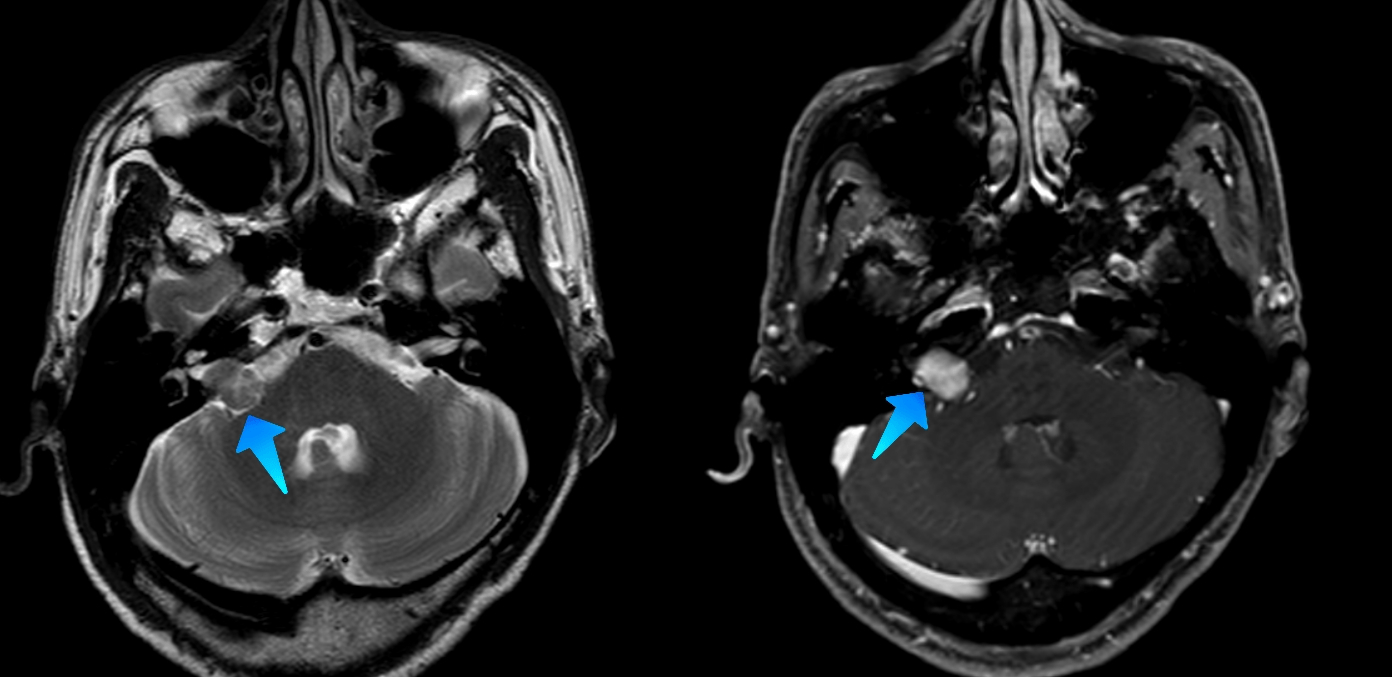

【高尚病例】听神经瘤 1 例

图片尺寸1080x1080